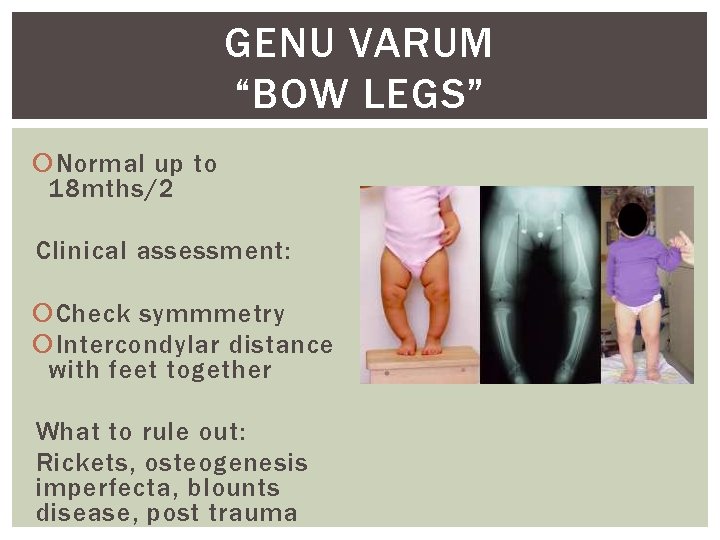

GENU VARUM “BOW LEGS” Normal up to 18 mths/2 Clinical assessment: Check symmmetry Intercondylar distance with feet together What to rule out: Rickets, osteogenesis imperfecta, blounts disease, post trauma